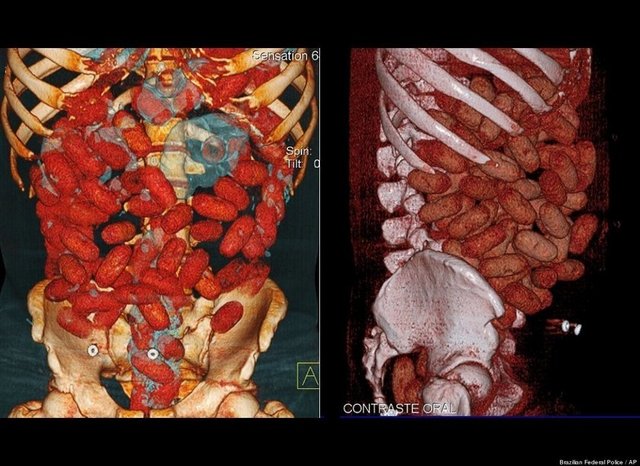

"Özellikle havaalanlarındaki girişlerde iki tür cihazı da görebiliriz. Eşyaların geçirildiği X-Ray cihazında X ışınları kullanılarak görüntüleme yapılır. Çantaların içinde ne olduğu X ışınları ile görüntülenir. Burada uygulanan X ışınlarının eşyalara bir zararı yoktur, birikmez, eşyalarda radyasyon kirliliği yapmaz. Bu cihazların çevresi X ışınlarının insanlara zarar vermemesi için kurşun paravanlarla kaplıdır."